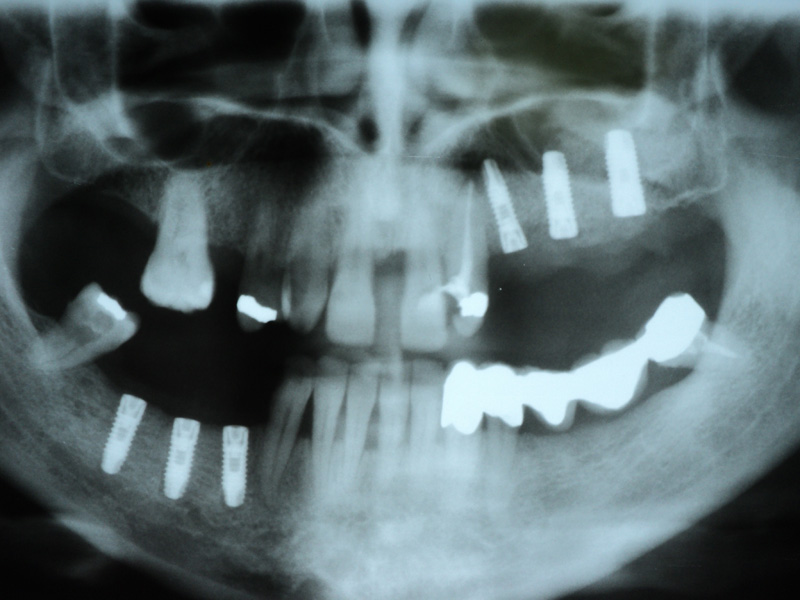

Radio-

grafii

Implante - Galerie Foto